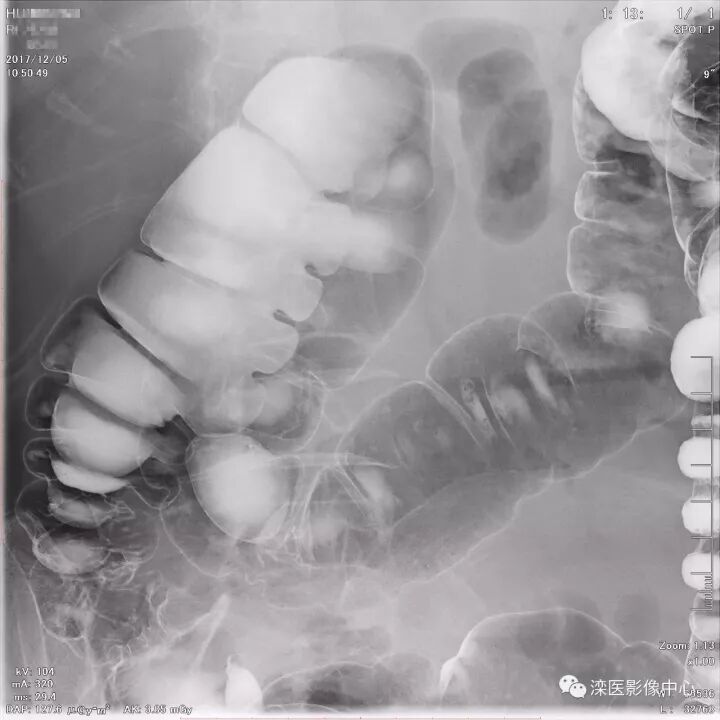

下面请您审阅近期我院影像科开展下消化道双对比造影检查的图像:

(俯卧位观察直肠、乙状结肠及降结肠)